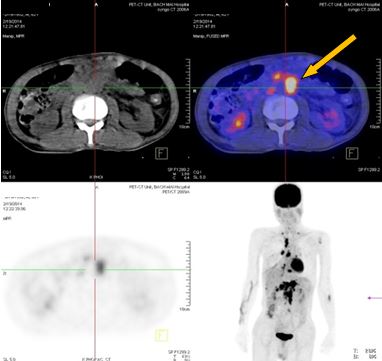

+ Nhiều hạch ổ bụng dọc theo ĐM chủ bụng tạo thành khối lớn KT 8,5x5,1 cm và 5,1x3,9cm, tăng hấp thu F-18 FDG, max SUV=10,45. Nhu mô gan hạ phân thùy VI có nốt KT 1,2cm, tăng hấp thu F-18 FDG, max SUV=4,15.

-Trước điều trị: Nhiều hạch ổ bụng dọc theo ĐM chủ bụng tạo thành khối lớn KT 8,5x5,1 cm và 5,1x3,9cm,  max SUV=10,45.

-Sau điều trị 4 tháng: Không có hạch ổ bụng

Trước điều trị: Hạ phân thùy VI gan P có nốt 1,2cm, max SUV= 4,15. Hạch ổ bụng: 8,5x5,1 cm  max SUV=10,45

Sau điều trị 4 tháng: Không có tổn thương